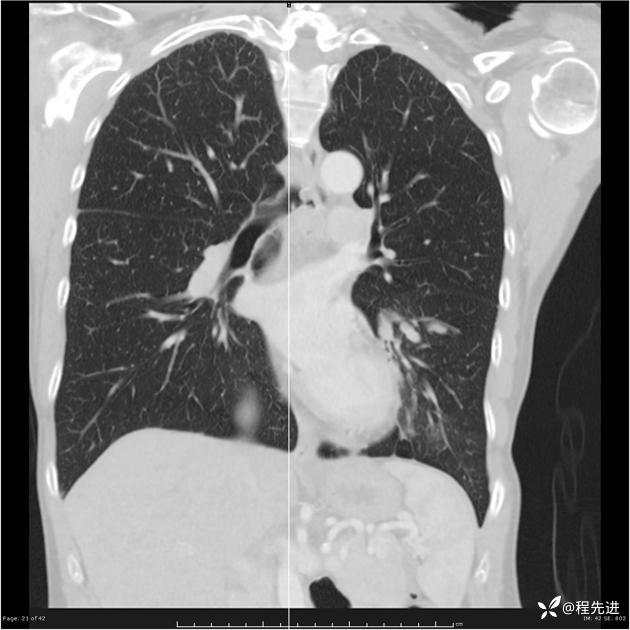

病例女,53岁,气管、左主支气管、下叶支气管内结节,乳头状瘤?期待你的精彩解读

女,53岁

乳头状瘤?